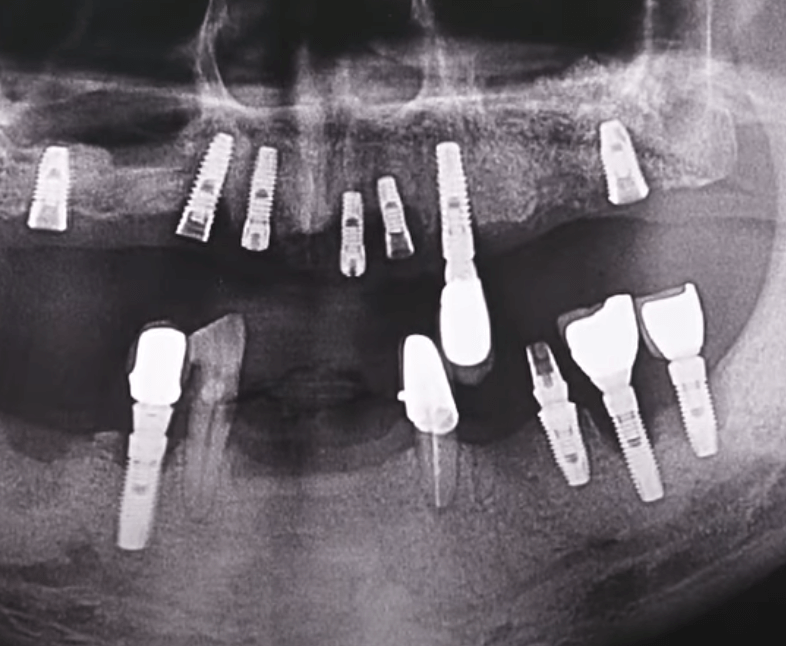

개인적으로 임플란트를 2개를 식립 받은 사람으로 그동안 별다른 부작용 없이 잘 사용하고 있습니다. 임플란트 시술 세계 1위 국가인 국내에서도 대중화가 되며 이를 통해 다시 씹는 즐거움을 되찾은 사람들이 많아지고 있습니다. 하지만 임플란트는 식립이 완료되었다고 해서 모든 과정이 끝나는 것이 아니기 때문에 꾸준히, 지속적으로 관리를 해주는 것이 중요합니다. 만약 관리가 소홀할 경우 잇몸이 녹아내리거나 나사 주변의 염증으로 경우에 따라서는 제거를 하고 브릿지를 해야 하는 경우도 발생하기 때문에 경각심을 가지고 관리하고 주의하는 것이 좋습니다. 오늘은 임플란트 주위염의 원인, 증상, 예방 및 관리방법에 대해서 자세히 살펴보도록 하겠습니다.

임플란트 주위염은 임플란트 수술 후 발생할 수 있는 주요 합병증 중 하나로, 특히 구강 위생이 소홀해지면 자주 나타날 수 있는 증상입니다. 이 질병은 주로 치주에 대한 관리가 부족할 경우 발생하며, 이로 인해 어렵게 심은 임플란트가 뽑히거나 탈락하는 등의 부작용을 유발할 수 있습니다. 임플란트 주위염은 일반적으로 치주염과 유사한 증세를 보이며 초기에는 발견이 어려울 수 있습니다. 이러한 이유로 정기적인 검진이 더욱 중요하며, 초기에 증상을 발견하여 조기에 대처하는 것이 필요합니다.

만약 임플란트가 흔들린다면, 이는 크게 두 가지 주된 원인으로 나뉩니다. 첫 번째로는 임플란트를 구성하는 나사가 헐거워져서 풀어지는 경우입니다. 이 경우에는 나사를 다시 적절히 조이면 문제를 해결할 수 있으며, 비교적 간단한 조치로 신속한 치료가 가능합니다. 그러나 두 번째로, 임플란트 주위염이 원인인 경우에는 상황이 다릅니다. 임플란트 주위염은 임플란트와 치조골 사이의 골 결합이 파괴될 때 발생하며, 이 경우에는 임플란트를 다시 수술하여 재픽싱하는 것이 필요할 수 있습니다. 이는 좀 더 복잡한 치료를 필요로 하며, 빠른 대응이 요구됩니다. 따라서 임플란트의 느슨함이 발견되면, 원인을 신속히 확인하여 적절한 치료 방법을 찾는 것이 중요합니다.

임플란트는 현재로서 자연 치아를 대신할 수 있는 가장 효과적인 방법 중 하나로 인정받고 있습니다. 그러나 임플란트 주위염이 발생하면 임플란트를 제거하고 재식립하는 과정은 간단하지 않기 때문에 초기부터 신중한 관리가 필요합니다. 특히 정기적인 치과 검진이 매우 중요한데, 외부적으로는 문제가 없어 보이더라도 실제로 치조골이 손상되어 있는 경우가 있을 수 있습니다. 따라서 치과 전문의의 꾸준한 감독과 세심한 관리를 통해 임플란트가 오랜 기간 동안 튼튼하게 유지될 수 있도록 하는 것이 핵심입니다.

임플란트를 시술한 이후 3개월에서 6개월 사이에 정기적인 검진을 받는 것이 매우 중요합니다. 특히 임플란트 주위염은 초기에는 육안으로 쉽게 발견되지 않으며, 겉으로 나타나는 증상이 미미하기 때문에 문제를 미처 감지하지 못하고 방치하다가 심각해질 수 있는 가능성이 큽니다. 이에 검진을 통해 치조골의 상태를 주기적으로 확인하는 것이 좋습니다. 또한, 스케일링은 국민건강보험을 통해 매년 1회 지원을 받을 수 있어 치아와 임플란트, 잇몸 사이사이에 쌓인 치석을 효과적으로 제거해주어 구강 위생을 유지하는 데 큰 도움이 될 수 있습니다. 따라서 이러한 정기적인 검진과 스케일링은 임플란트의 오랜 기능과 안정성을 유지하는 데 핵심적인 역할을 합니다.